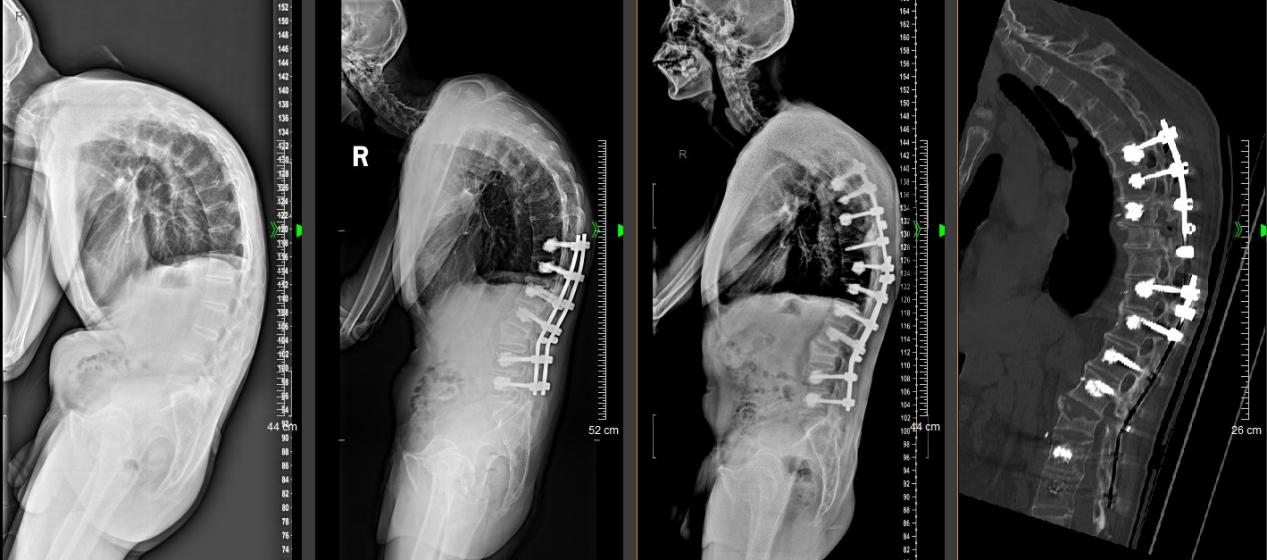

术前影像学检查提示,赵先生脊柱参数严重失去平衡,严重的脊柱后凸导致赵先生腹部严重皱褶、胸骨凸入腹腔、胃肠等消化器官受压,且虽然才40岁,但骨头质量却如80岁的老人,手术挑战巨大。

经过全科疑难讨论,黄敏军最终决定为赵先生实施分期脊柱后凸矫形手术:第一期先实施经腰2椎体四级截骨矫形手术,术后半年再行第二期更为复杂的胸椎经椎弓根截骨后凸矫形手术,尽可能获得水平视野、实现平卧睡觉。

2024年7月和2025年5月,赵先生先后接受了两次手术,手术后,他的脊柱终于伸展了。黄敏军查房时表示,矫形不足会导致患者无法获得水平视野,无法实现平卧睡觉,过度矫形又会导致以后无法看到脚尖,走路也会受影响,手术可谓努力寻找平衡点。